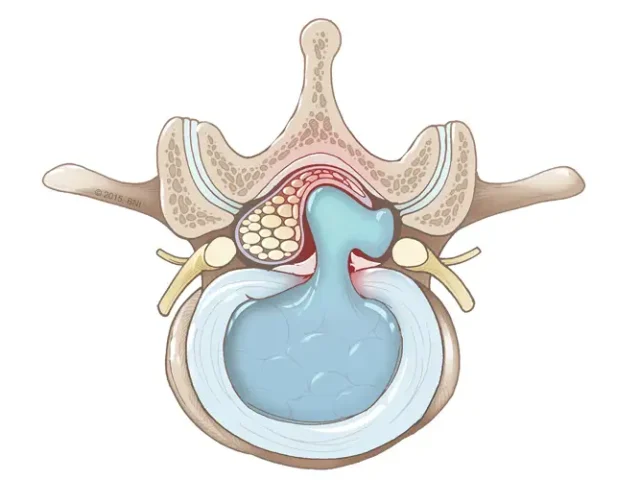

تزریقات داخل مفصلی

روشی کم تهاجمی برای کاهش درد و التهاب مفاصل است که معمولا با داروهای استروئیدی یا هیالورونیک انجام می‌شود. این روش به بهبود حرکت مفصل و کاهش نیاز به جراحی کمک می‌کند.